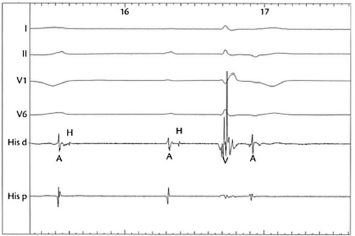

O cateter quadripolar foi retraído para a região do feixe de His, revelando o traçado mostrado na segunda figura.

Figura 2: